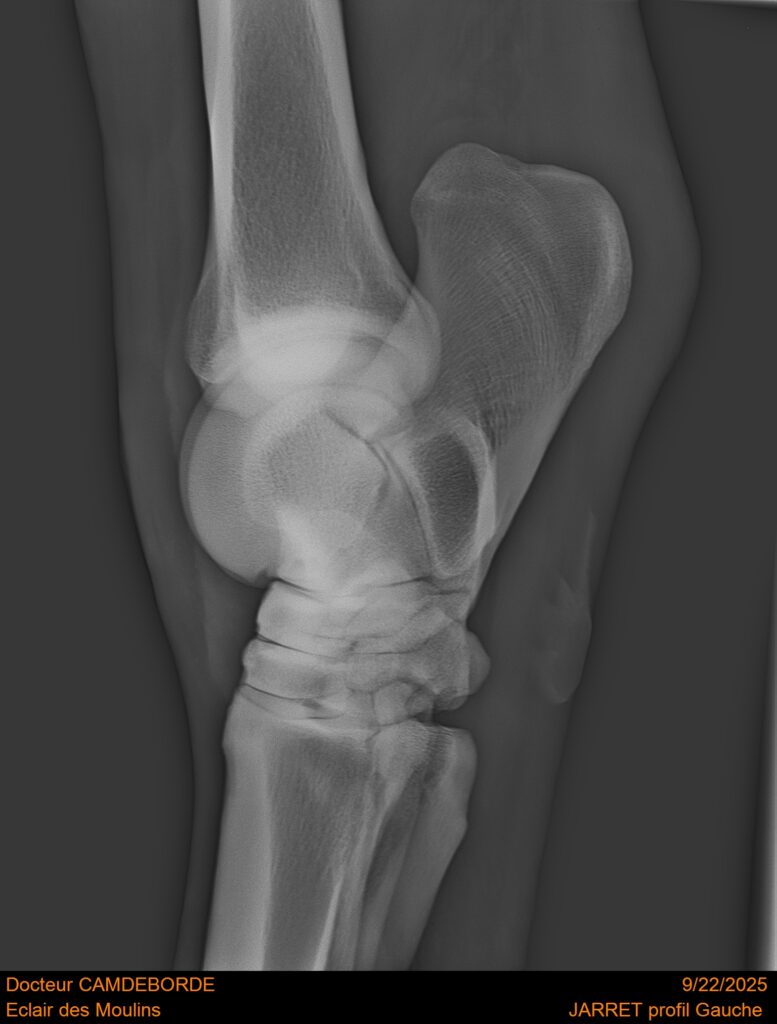

10 K ✨ TOP cheval pour épreuve Amateur ! ECLAIR DES MOULINS, selle Français de 11 ans. Classé sur 1m05. Idéal pour aller faire jusqu’à 110 voir 115, cheval pas usé (une vingtaines de parcours). Très gentil au quotidien, cheval de famille. Courageux et respectueux à l’obstacle. Bien dressé, change de pieds. Bilan pieds, boulets, jarrets, grassets et visite clinique effectuée cette semaine. il peut vivre au box comme au champs, cheval rustique. toise environ 1m60 porteur. Pour le compte de son propriétaire car manque de temps.

RADIOS ET CLINIQUE